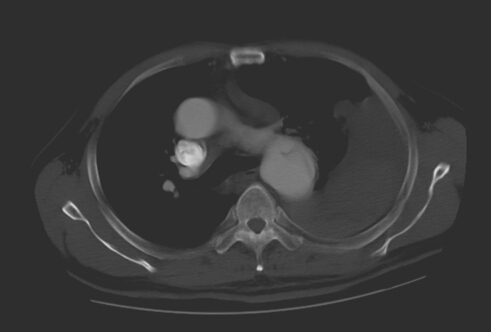

術后見支架位置良好,將破口隔絕,胸腔積液明顯減少

各相關科室醫(yī)護人員迅速準備到位,成立搶救小組,各司其職。鄭翼德主任在大血管介入治療方面有著豐富的經驗,搶救小組經過仔細討論研究,決定對患者實施胸主動脈帶膜支架腔內隔絕術。緊急氣管插管、麻醉、股動脈切開、主動脈造影,一切都有條不紊地進行。透視監(jiān)視下,導絲導管從股動脈進入,向上“游”走到升動脈弓處,造影明確夾層破口位置及撕裂情況,選取適當支架系統(tǒng),在支架穩(wěn)穩(wěn)妥妥地放入預定主動脈內后,再次造影顯示破口完全封堵,未見經內漏繼續(xù)出血,手術取得圓滿成功。大家雖然苦了、累了,汗流浹背,卻個個露出了開心的笑容。

然而,術后道道難關依然險象環(huán)生。由于當時動脈瘤破裂時,大量血液涌入胸腔致胸腔積血、肺組織實變,同時并發(fā)肺部感染,加之患者高齡、基礎疾病多,營養(yǎng)狀況差,術后,患者一度感呼吸困難,并出現(xiàn)發(fā)熱、肝功能損害、胃腸功能紊亂、泌尿系感染等,一系列與正常指標“嚴重背離”的化驗、監(jiān)測結果,無不提示著老人正瀕臨生死關口,多次請相關科室會診, 從不同角度商討治療方案,最終通過胸腔穿刺引流、控制性降壓、減慢心率、抗細菌感染、靜脈營養(yǎng)支持、輸血、化痰、保肝、調節(jié)腸道菌群、止瀉、通便……等一系列治療措施,通過整整56天醫(yī)護人員每天24小時的“全天候”保駕護航,一個個難題被一次次化解,終于將患者從死亡線上拉了回來,轉危為安。